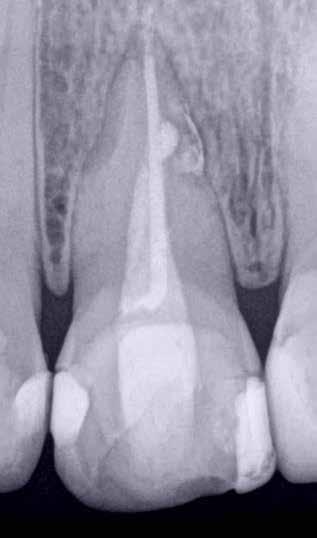

Nagyon fontos, hogy már a kezelések elején meghatározzuk, hogy melyek azok a hiányzó fogak, amelyeket a későbbiekben pótolni szeretnénk, valamint helyesen diagnosztizáljuk a kariológiai, endodonciai vagy parodontológiai okok miatt ellátást igénylő elváltozásokat. Szintén kiemelt jelentőséggel bír a fogak megtarthatóságának kiértékelése. A kezelési terv felállítása során tisztában kell lennünk azzal, hogy mely fogak alkalmasak fogpótlások ideiglenes vagy végleges elhorgonyzására.

A preprotetikai fázisban el kell látnunk a diagnosztizálásra került kórfolyamatokat, megfelelő pozícióba kell állítanunk a megtartani kívánt fogakat, pótolnunk kell az elvesztett csontállományt, valamint gondoskodnunk kell az íny megfelelő állapotáról. Ha szükség van rá, úgy a foghiányok pótlására szolgáló dentális implantátumok is ebben a fázisban kerülnek behelyezésre. Általánosságban elmondható, hogy azokat a kezeléseket, amelyek befejezése biológiai okok miatt hosszú időt vesz igénybe (pl.: fogszabályozás, csontpótlás, implantáció), a lehető leghamarabb érdemes elkezdeni.

A fogszabályzó kezelések egyik legfontosabb célja, hogy elérjük a lehető legharmonikusabb interokkluzális fogérintkezéseket, továbbá az állcsont relációs helyzetének frontális és szaggitális síkban is megfelelőnek kell lennie. A fogszabályzás befejezésekor a fogpozícióknak nem orthodonciai, hanem protetikai szempontok szerint kell ideálisnak lenniük. Az Invisalign ClinCheck szoftver (Align Technology) segítségével a protetikus az orthodontussal együtt meg tudja határozni azokat a végső fogpozíciókat, amelyek a lehető legjobb végeredmény biztosításához elengedhetetlenek. Bizonyos klinikai paramétereket, mint a fogak klinikai koronájának nagyságát, az egyes fogak fogíven belüli optimális pozícióját, a fogívek egymáshoz viszonyított helyzetét, a fogak között látható rések nagyságát, a frontfogak tengelyének dőlését, az overjet és overbite mértékét már a kezelések megkezdése előtt pontosan definiálni kell. Ezeket az adatokat viszont csak a tervezett végleges fogpótlás ismeretében lehet meghatározni, ezért van szükség az orthodontus és a protetikus szoros együttműködésére.